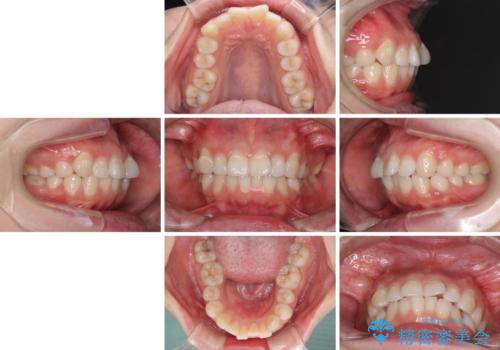

- 前歯のデコボコを気にして来院された患者様です。

当初は口元の突出感はあまり気にされていない様子だったので、インビザラインによる非抜歯矯正をお勧めしたが、ふっくらとした口元を改善したいとのことで、積極的に口元の突出感を改善することとしました。

上下左右第一小臼歯4本の抜歯を行い、ワイヤー装置による矯正治療を行うこととしました。

元々上下正中の位置はずれていましたが、治療中によりズレが大きくなったので、元の位置に戻すため治療期間を余計に要しました。

横顔の印象が大きく改善され、患者様には大変満足していただきました。